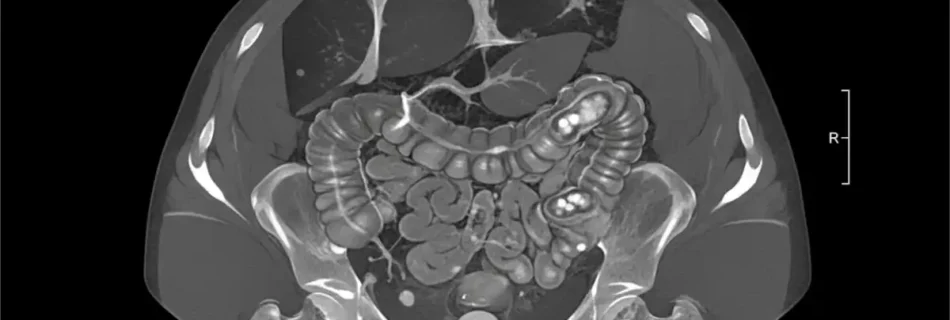

Appendicitis CT: Complete Guide to Diagnosis and Imaging

Introduction Doctors rely on modern imaging to diagnose abdominal emergencies quickly. Imaging reduces risks and improves treatment outcomes. appendicitis ct plays a key role in confirming inflammation of the appendix. It helps doctors avoid misdiagnosis and unnecessary surgery. This guide explains how CT scans detect appendicitis, what to expect, and why accuracy matters. What Is …